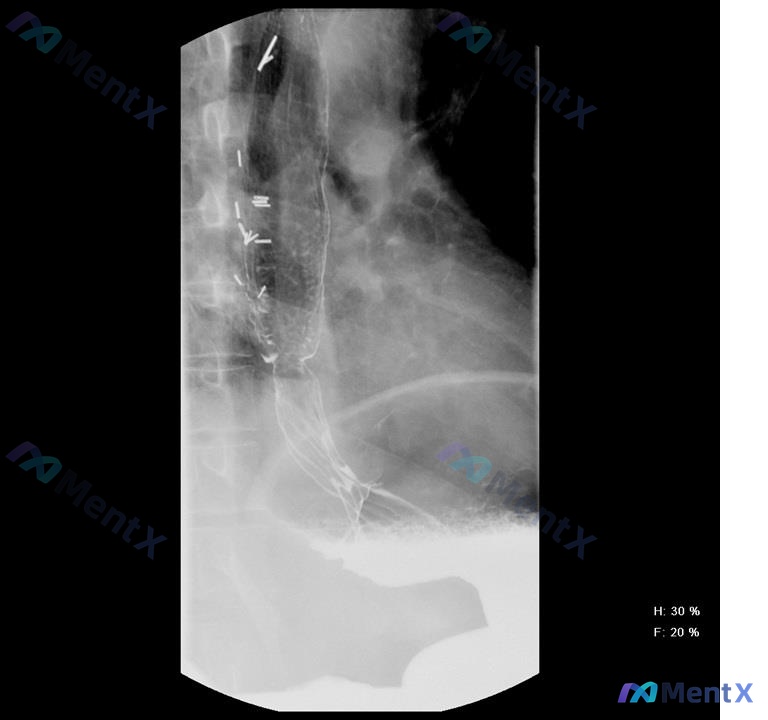

- 食管中上段管腔扩张,中下段可见一处明显狭窄

- 食管内有明确的圆柱状网格结构影

- 造影剂能通过网格结构向下,但到远端狭窄处通过明显变慢,呈细线状通过

- 未见明确造影剂溢出到纵隔或气管的情况

📋答案:当前最确切的临床诊断为:食管支架植入术后伴远端再狭窄(高度怀疑肿瘤复发或食物嵌塞);基础病因高度提示为食管癌进展期。